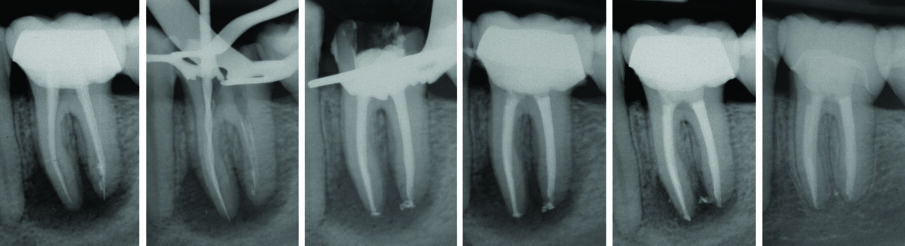

Il primo passaggio nell’esecuzione della tecnica M-seal consiste nella scelta di un cono di guttaperca avente conicità .02 di diverso diametro di punta che si adatti alla preparazione apicale. Esso, lo si compatta con uno Spreader in nichel titanio con diametro di punta #25 e conicità .04 (Fig. 4) ad una velocità di 300 rpm consentendo al cono di prendere contatto con la parete canalare esclusivamente a livello dell’ultimo millimetro apicale, lasciando uno spazio sufficiente alla seconda fase dell’otturazione. Per questo motivo è consigliabile usare sempre un cono di conicità .02: coni di conicità maggiore, infatti, potrebbe ridurre eccessivamente lo spazio per la fase successiva. La scelta e l’adattamento del cono master all’apice viene effettuata secondo le modalità note per la tecnica di condensazione laterale: si deve selezionare un cono che si venga ad arrestare nell’ultimo mm della preparazione “stop dinamico” impegnandosi nella preparazione apicale, dando origine alla nota sensazione del “tug-back”. Il corretto posizionamento del cono di guttaperca all’apice deve essere verificato radiograficamente (Fig. 5).

Figg. 5 - A, rx preoperatoria 3.5 cura incongrua, B dopo strumentazione prova cono ad 1 mm, C cono master diametro in punta 45 con cemento, D rx dopo aver condensato il cono master mediante spreader in NiTi, E rx dopo otturazione mediante guttaperca plasticizzata.